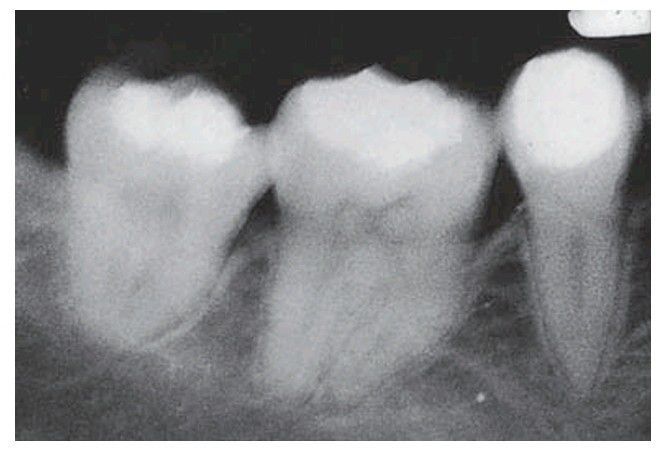

Multiple pulp stones in a case of Ehlers–Danlos syndrome.